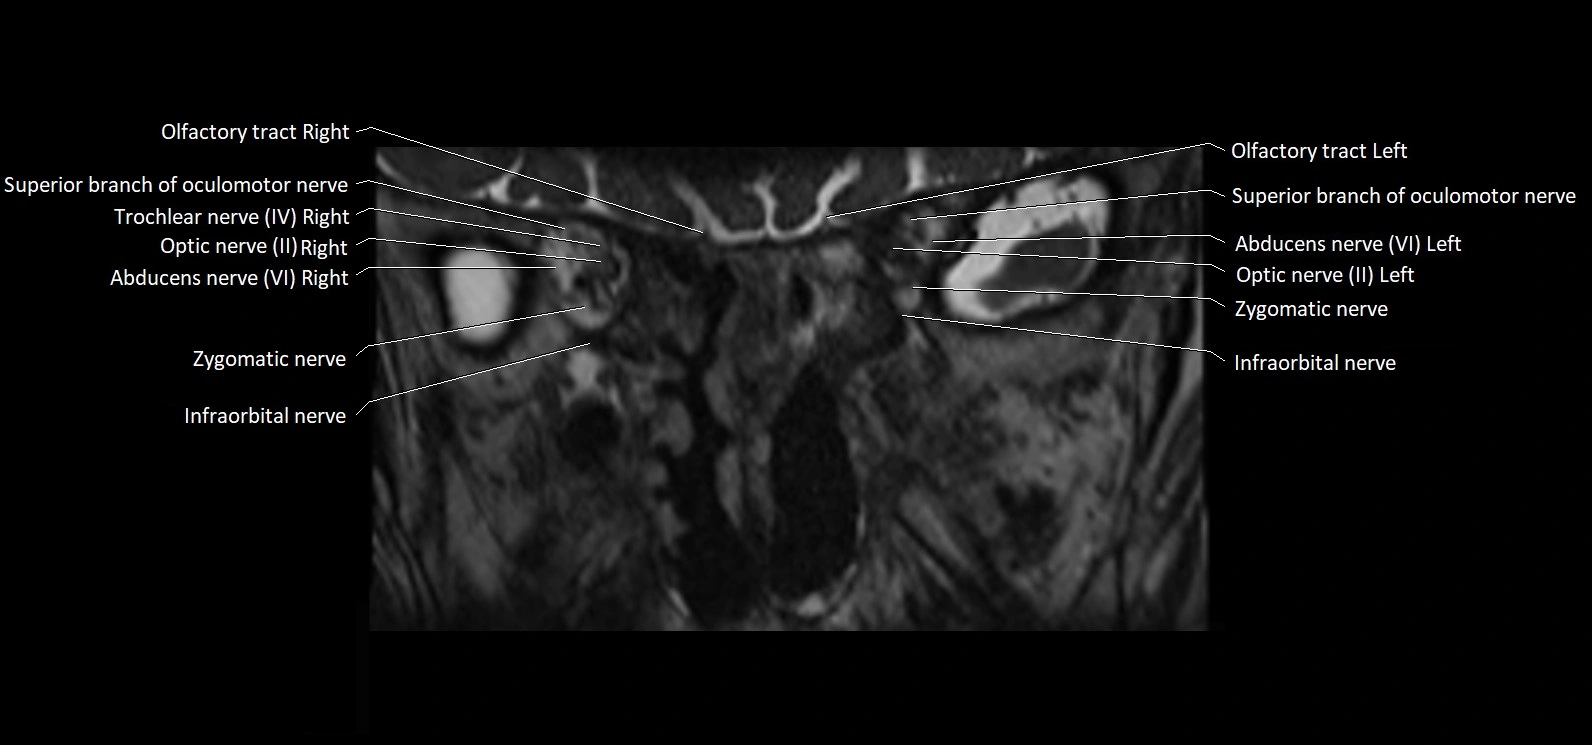

MRI Appearance

• The abducens nerve is a small, thin, linear structure

• Best visualized on high-resolution T2-weighted 3D MRI sequences (e.g., FIESTA or CISS)

• Seen as a hypointense (dark) line running from the brainstem at the pontomedullary junction, traversing the prepontine cistern, and entering Dorello’s canal under the petrosphenoidal ligament, then into the cavernous sinus, and finally the orbit

• May be challenging to visualize in standard MRI due to its small size

• Pathology may be inferred by absence, displacement, or enhancement of the nerve

MRI images

image